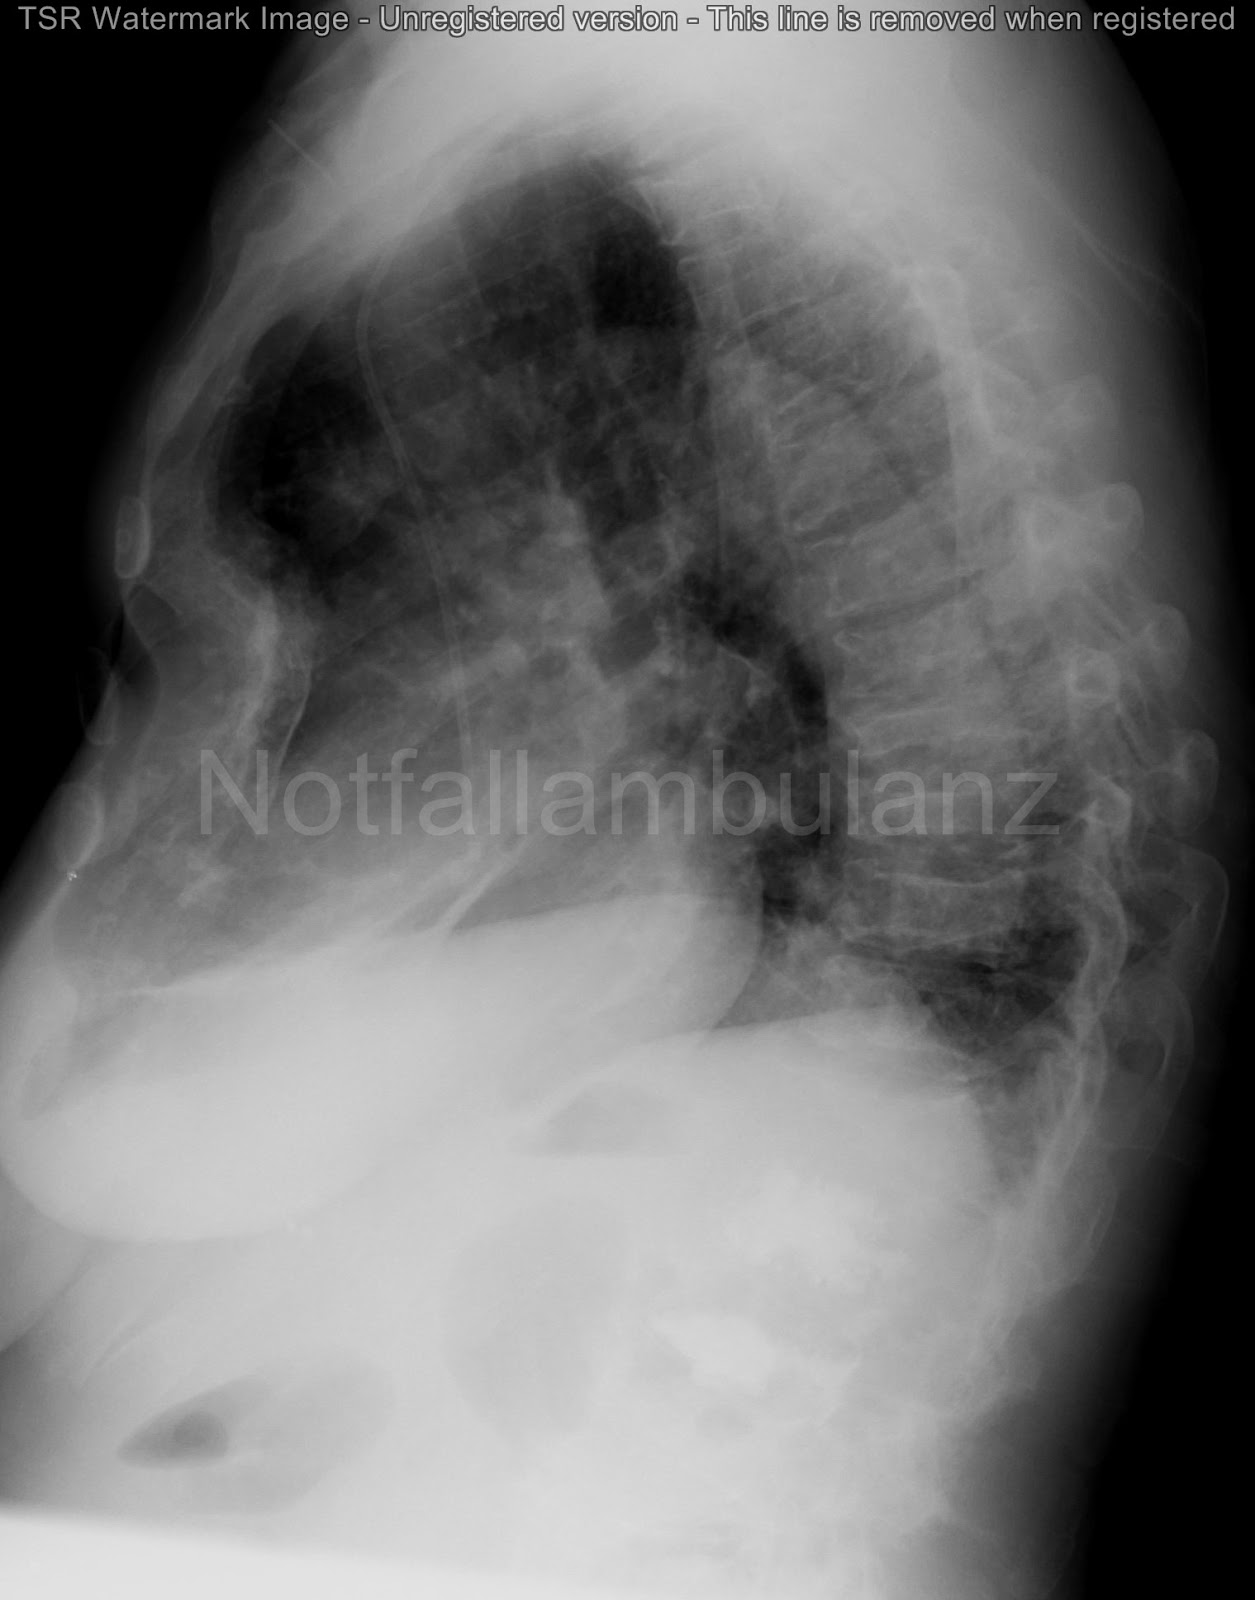

Fall 54: Der unerwartete Brustschmerz

Ein 65-jähriger Mann stellt sich abends in der Notaufnahme vor. Seit 4 Wochen bestünden Ruhe- und belastungsabhängige thorakale Schmerzen in der Wirbelsäule. Die Schmerzen weckten ihn nachts auf und wären von einem dumpfen Charakter. Die Schmerzen hätten sich jedoch seit kurzem ausgebreitet und die gesamte Wirbelsäule erfasst.

Der Hausarzt hätte wegen bewegungsabhängiger Rückenschmerzen die Diagnose eines BWS-Syndroms geäußert. Ein Röntgenbild wurde nicht angefertigt, auch keine weiterführende Diagnostik.

Anamnestisch habe sich das Allgemeinbefinden verschlechtert. Der Patient gab eine Leistungsschwäche und Erschöpfung mit einem Gewichtsverlust von 2 kg in den letzten 4 Wochen an. Auch schwitze er nachts. Neurologische Symptoms mit Schwäche oder Blasen- Mastdarmschwäche wurden verneint.

Laborchemisch zeigt sich eine normochrome Anämie, eine Erhöhung der alkalischen Phosphatase und des Kalziums sowie eine dreistellige Erhöhung der BSG. Herzfermente sind unauffällig.

Das EKG kann eine Ischämie ausschließen.

Radiologisch findet sich folgender Befund im Thoraxbild: